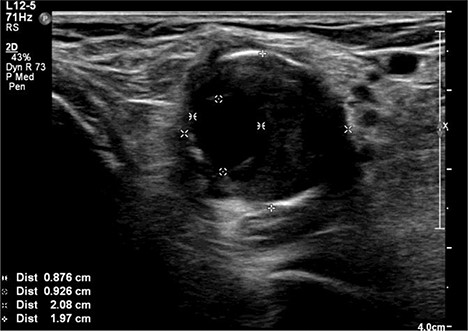

A 92-year-old female, independent from home, presented after multiple falls due to a four-month history of left foot drop. The foot drop had gradually worsened to the point that there was complete paralysis of ankle dorsiflexion and was associated with significant oedema of the foot. On examination, there was a large pulsatile mass in the popliteal fossa bilaterally. All peripheral pulses were palpable without any signs of ischemia. The most striking examination finding was complete paralysis of left ankle dorsiflexion with 0 out of 5 power. Ultrasound revealed that there were (Fig 1) bilateral popliteal artery aneurysms, which was larger on the left, causing displacement and impingement of the common peroneal nerve at the knee crease (Fig 2). Further computed tomography angiogram demonstrated an unruptured left PAA measuring 22 × 21 mm in maximal dimension over a distance of 24 mm (Fig 3). Intraluminal thrombus was also noted with 60% luminal stenosis. Distally, the arteries were heavily calcified with two-vessel runoff at the ankle. An emergency endovascular repair of the left PAA was performed by using 8 mm × 15 cm and 7 mm × 10 cm Gore Viabahn stents (Fig 4). The stents were deployed after a balloon-angioplasty and adequate decompression of the aneurysm was achieved. The postoperative period was uneventful, and patient’s pre-existing aspirin was continued. The leg and foot oedema improved rapidly over the subsequent few days. At follow-up in 12 weeks, the patient showed some return of motor function of the ankle and was walking with ankle splint. Her left leg remained well perfused with palpable pulses.

Digital subtraction angiogram image of the endovascular repair of left popliteal artery aneurysm with 8 mm × 15 cm and 7 mm × 10 cm Gore Viabahn stents.